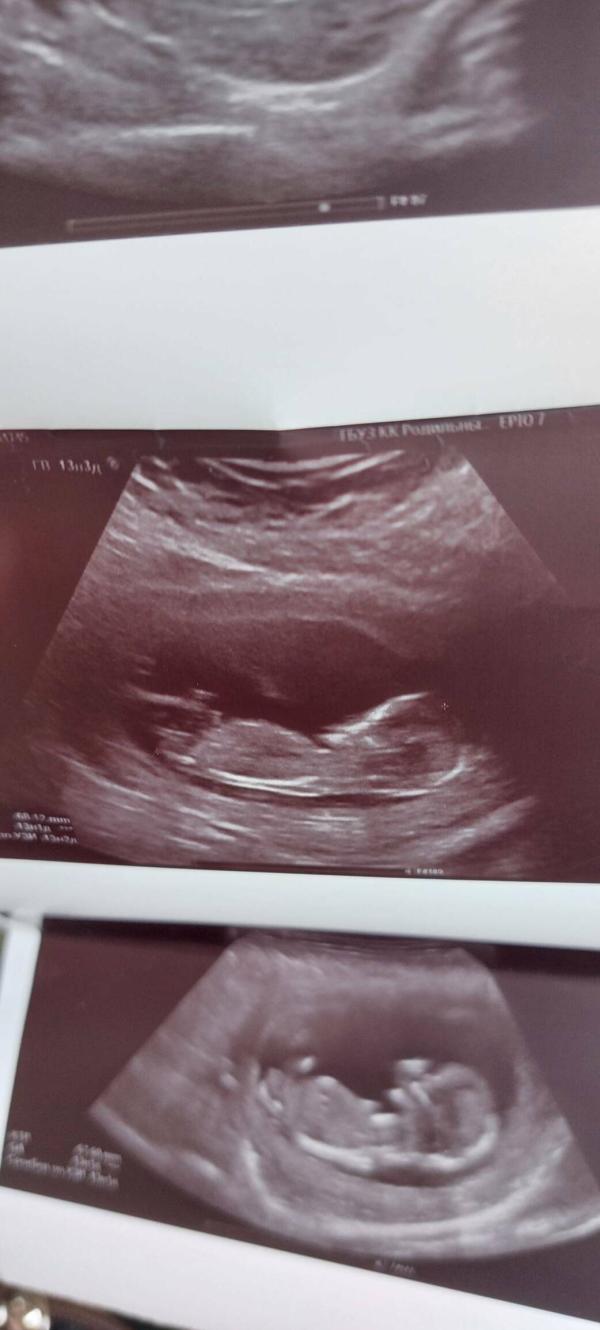

Вот и первый скрининг. У нас все хорошо, по сроку УЗИ догнали акушерский срок. Муж был рядом, даже немного всплакнул. Малыш расти крепким, сильным и здоровым, мы с папой тебя очень любим и очень ждём тебя в этот удивительный мир 👼👩❤️👨

По половому бугорку, угол наклона лобковой кости по отношению копчика, тут она паролельна...что указывает на девочку, утверждать не буду, но очень похоже)

Если честно, я тоже это видела. Есть видео, там прям есть момент, где очень хорошо видно))) мы больше девочку хотим, за 2м за пасаном пойдем)